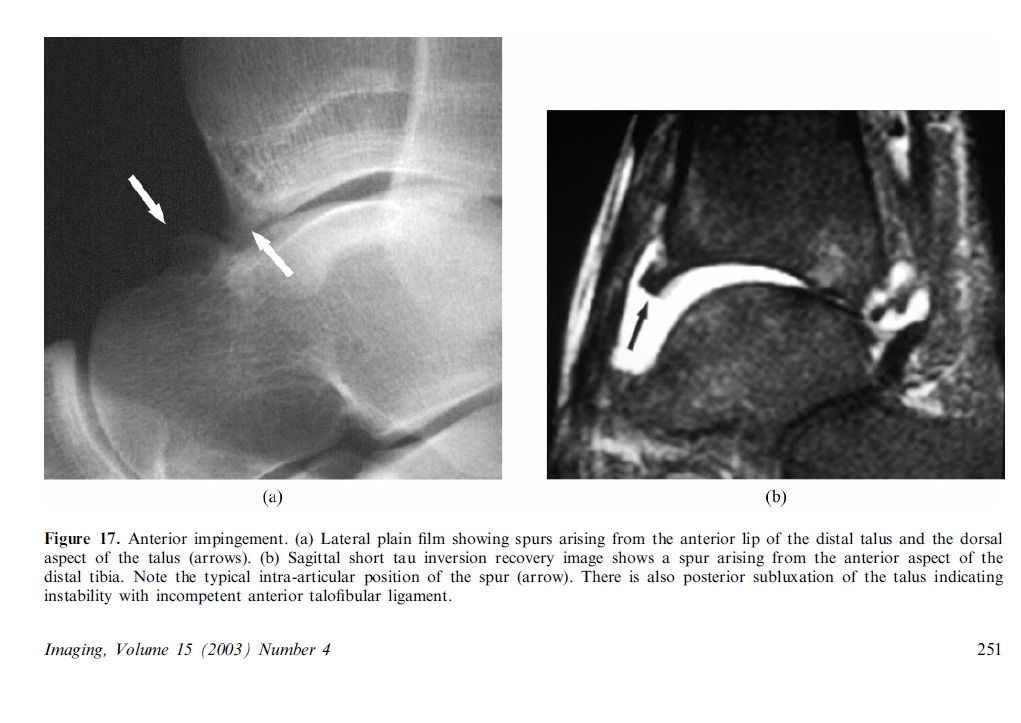

Imaging plays a major role in the management of ankle and foot problems. Most conditions are assessed by plain

films alone. MRI is an excellent technique for those cases where the diagnosis is uncertain as it can exclude most

clinically relevant pathologies. Ultrasound is an excellent tool for imaging focal soft tissue abnormalities. CT is

occasionally useful when bony detail is required. Bone scintigraphy has a limited role and has been largely replaced by MRI in many centres. The main reasons for referral are swelling and pain. Many conditions of the ankle and foot are related acute or repetitive trauma.